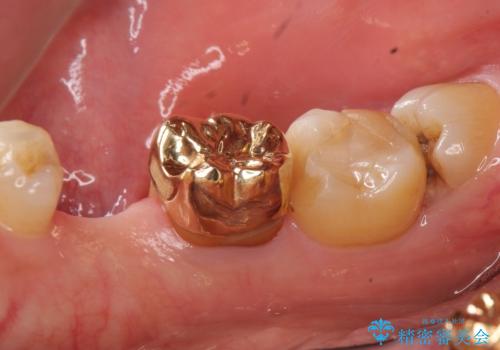

親知らずを抜歯して隣の歯のう蝕を除去し、歯肉の治癒をしっかり待ったのち、患者様のご希望によりゴールド(PGA)クラウンによる補綴を行いました。

右下7:ゴールド(PGA)クラウン